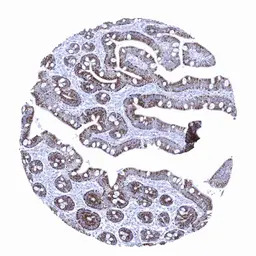

IHC-P analysis of human liver tissue section using GTX04478 Hepatocyte Specific Antigen antibody [MSVA-OCE5] HistoMAX.

Moderate to strong Hepatocyte immunostaining in epithelial cells of the duodenum.